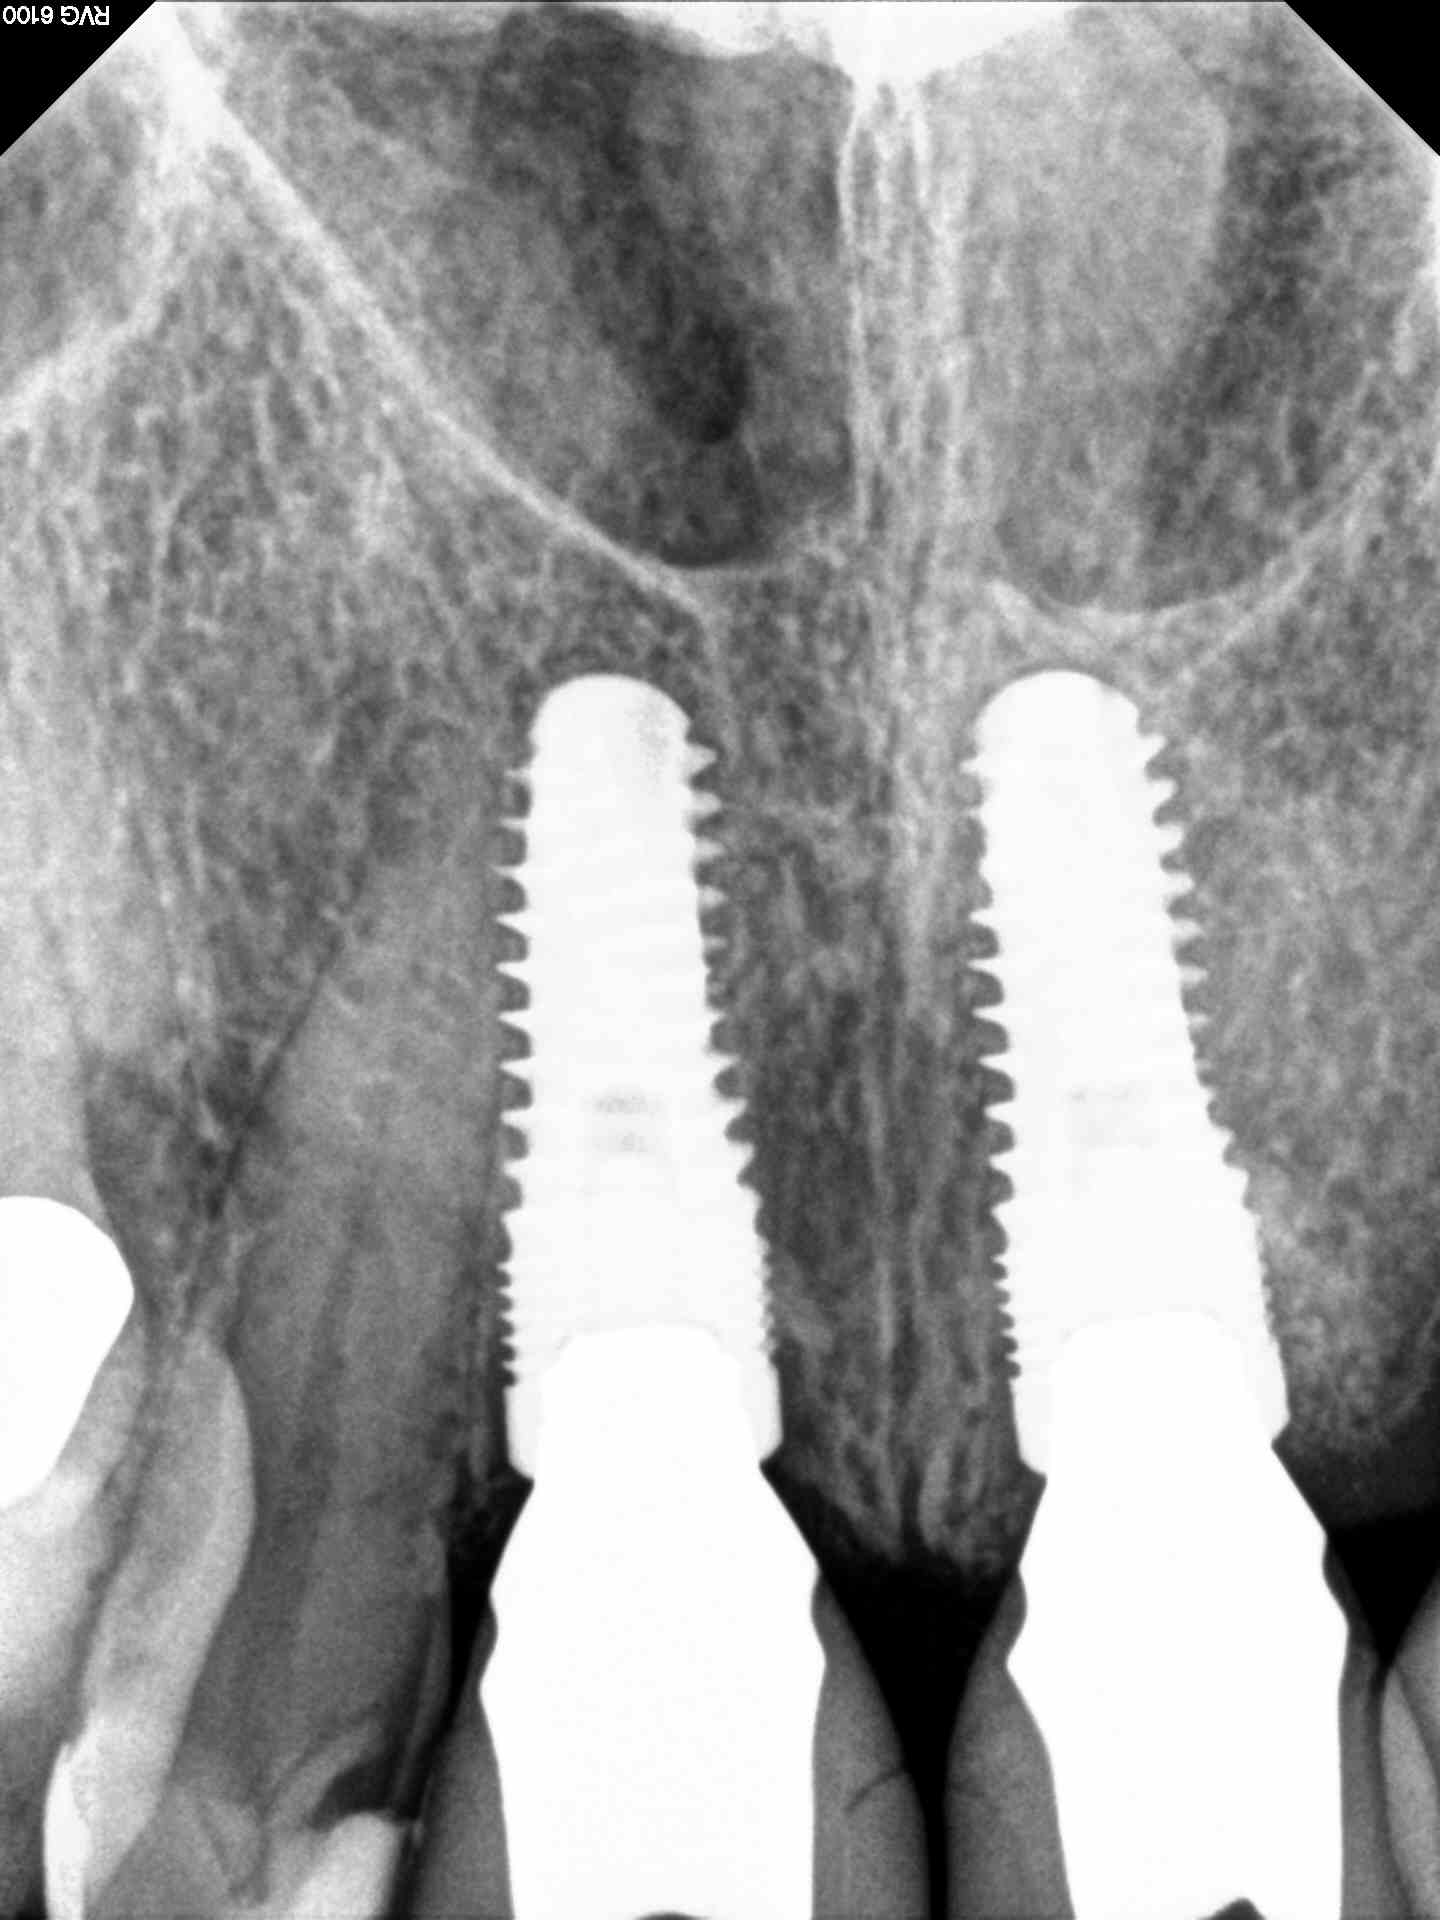

Accordingly, the patient enrolled in the multicenter study in December 2011. She opted for extraction, immediate provisionalization, and immediate loading, and visited both the oral surgeon (JMA) and prosthodontist (MAP) authors’ practices on the same day in January 2012 to consolidate these phases. Teeth Nos. 8 and 9 were extracted under local anesthesia (infiltration with lidocaine 2% with 1:100,000 epinephrine, 3.6 mL). The crowns were removed, then the roots were elevated and extracted. Osteotomy was made in type II (moderate) bone with Class A bone quality; all socket walls were intact. After tapping the sites, two 4.5-mm x 13-mm tapered implants (Genesis) were placed with primary stability of 40 Ncm (Figure 21) and 5-mm healing covers were placed (Figure 22 and Figure 23). The buccal socket gaps were grafted with spongious bone substitute (Bio-Oss®, Geistlich Pharma North America, www.geistlich-na.com). The gingival margins were reapproximated with 4-0 chromic sutures. Postoperative radiographs confirmed proper positioning in the alveolar bone.

The final impression (closed tray) was obtained in April 2012. The final ceramic crowns (IPS e.max Ceram) and custom porcelain-veneered, regular-diameter (RD) UCLA abutments (Genesis; and Creation CC, Jensen Dental, www.jensendental.com) (Figure 24, shown with PFM crowns and retention screws) were delivered in May 2012. Using a platform-switched connection, the abutments were torqued to 30 Ncm, the access holes sealed with Teflon, and the final crowns cemented with RelyX Unicem. Figure 25 through Figure 28 show the final IPS e.max Ceram crowns from periapical, facial, and incisal views, with a midfacial PD of 3 mm at the 18-month follow-up (Visit 7). A thick biotype is evident in Figure 26, as determined by the inability to detect the outline of the periodontal probe inserted below the restoration’s gingival margin.50 This image also demonstrates an excellent esthetic outcome.

Not unexpectedly, changes in interproximal marginal bone-to-implant distances between implant placement and final restoration (Visits 2 and 4, respectively) reflected minor crestal bone loss (≤ -2.03 mm). The greatest bone loss at this timepoint (-2.03 mm) was observed in Case 3, which involved the use of a xenograft bone substitute and placement of adjacent implants to replace two maxillary central incisors.

Between final restoration and 18-month follow-up (Visits 4 and 7, respectively), further bone loss of a much lesser degree was observed over all five cases (≤ -0.55 mm). Interestingly, Case 3 (which showed the greatest bone loss at Visit 4) also reflected small bone gains between Visit 4 and Visit 7 (Table 7).

Clearly, the crestal bone levels maintained 18 months postoperatively in Case 3 suggest a robust scaffolding effect provided by the xenograft material used during implant placement (Figure 25). To the authors’ knowledge, no direct clinical comparative studies have addressed differences that might be expected with xenografts versus allografts or autogenous bone. With regard to graft material and implant surface, a scanning electron microscopic study by Rocchietta et al identified no measurable differences in bone formation observed with xenografts relative to native bone, and no differences in bone apposition to oxidized versus machined implants.62